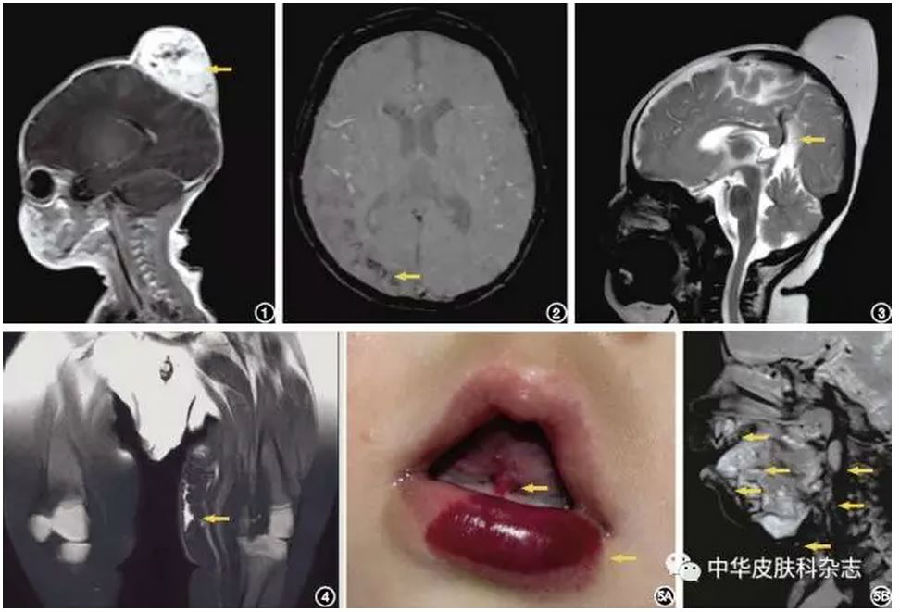

图1 颅顶部巨大血管瘤患儿磁共振成像增强扫描 黄色箭头处低信号为较大血管的流空效应 图2 颅颜面血管瘤综合征患儿磁共振成像 黄色箭头处为磁敏感序列右枕部皮层表面条状低信号影 图3 颅骨后顶部巨大血管瘤患儿磁共振成像 黄色箭头处为颅内有永存动脉窦 图4 静脉曲张

骨肥大综合征患儿磁共振成像 左下肢较对侧增宽,皮下脂肪层内有异常高信号影(黄色箭头) 图5 多部位深部毛细血管瘤 5A:下唇及舌系带均有毛细血管瘤(黄色箭头); 5B:患儿下唇、舌部、上颚、舌根、口咽后壁、口腔底部磁共振成像多处异常高信号(黄色箭头)

结果显示,105例患儿中男42例,女63例,年龄0.5 ~ 168个月,平均21.6个月。MRI检查发现,25例(23.8%)患儿有肉眼无法观察到的深部血管性病变,其中多部位深部毛细血管瘤15例,颅颜面血管瘤综合征4例,动静脉畸形3例,颅内永存动脉窦2例,静脉曲张骨肥大综合征1例。提示在儿科体表血管性病变临床诊断中,要警惕同时伴有深部血管性异常的可能,特别是表面血管瘤范围较大,或者位于特定部位,如三叉神经分布的区域,MRI检查可为诊断提供帮助。